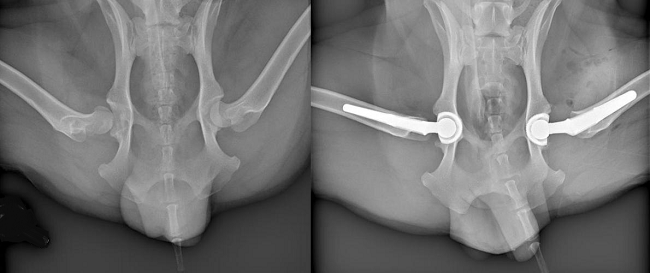

If pain cannot be controlled there are surgical procedures (right, above) which may relieve pain and improve function in some dogs. They include hip replacement, removing the femoral head (ball of the hip joint) and the acetabulum of the pelvis (hip socket) and replacing them with metal proteses. (See x-rays below.)

Hip "resurfacing" is an alternative to total hip replacement. Also called "coxofemoral hemi-arthroplasty", involves implanting a hollow cap*, shaped like a mushroom, over the head of the femur, and a matching metal cup in the pelvis socket.